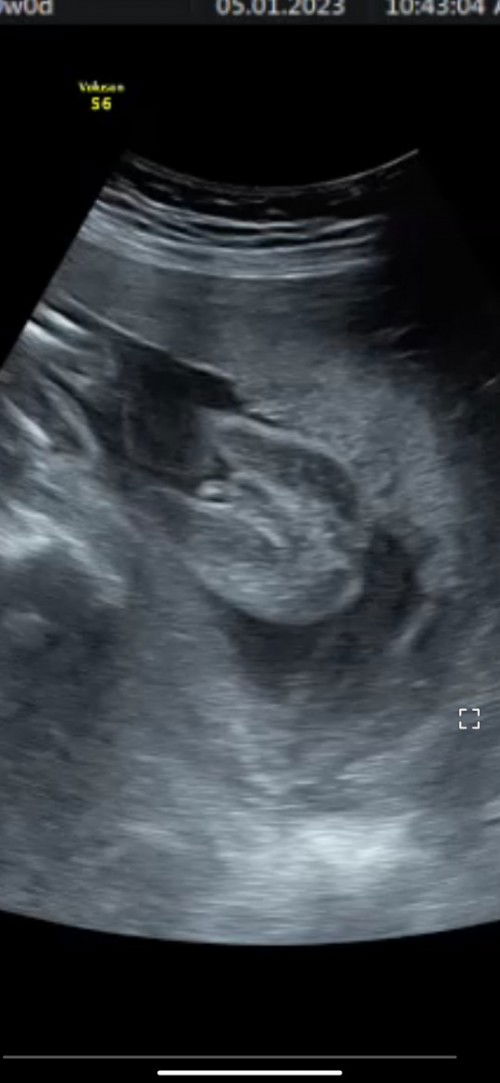

Kalau girl biasanya dia 3line & doc panggil burger. Tapi ikut gambar tu jelas baby boy, jika tak pasti boleh tanya yang lebih pakar next check up.

mcm boy.. hr tu sy pun mcm ni jugak doc cakap, nmpk bird😜😜

Nampak pistol tuu

mcm boy😊

Hehe mcm boy.

mcm boy

Baby boy

boy